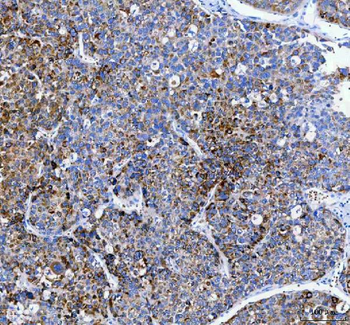

10 μg, 100 μgAnti-PAPSS2 Antibody [orb1743841]

ELISA, FC, IF, IHC, WB

Human, Mouse, Rat

Rabbit

Polyclonal

Unconjugated